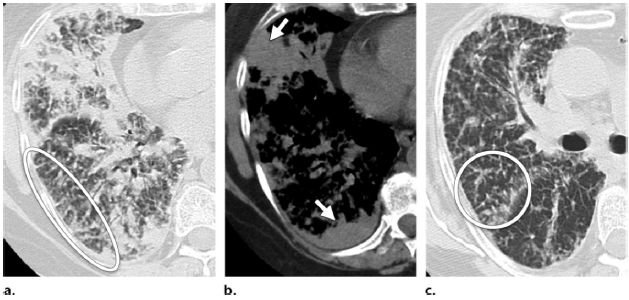

图4 患者,女,68岁,单克隆-γ球蛋白病,肺CT示与其有关的系统性淀粉样变性。一些区域间质性增厚(图a椭圆形区域),主要是肺外周及基底段的肺实变(图b箭头),斑片状磨玻璃影及肺实质微小结节(图c圆圈),这些改变均见于肺间质型淀粉样变性中。

肺泡间隔淀粉样变性的CT特点为边界清晰的2~4mm微结节,同时伴随网状影、小叶间隔增厚和以基底部、外周部分布为主的实变融合(图4)。肺点状钙化、胸水和胸膜增厚也可能出现(图5,6)。肺囊性病变少见,常见于系统性淀粉样变性患者表现Sjögren综合征时。囊性变可能与钙化或无钙化的软组织结节有关,但是形成机制不明,可能是由于Sjögren综合征导致的淋巴细胞性间质性肺炎